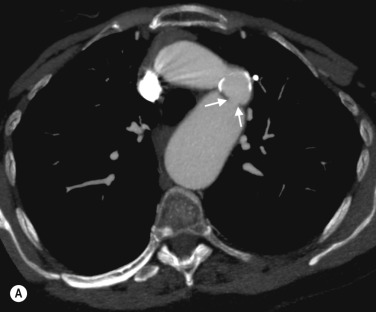

CTA is the investigation of choice for diagnosing acute aortic dissection, particularly in unstable patients, and for determining the extent of the flap. MRA offers similar information and in stable patients also gives excellent cardiac functional assessment. In patients presenting with suspected acute dissection but no flap on CT, MR can demonstrate intramural haematoma, although the penetrating ulcers that often lead to this condition are also well shown on CT ( Fig. 77.3 ).

Fig. 77.3, Acute Aortic Dissection.